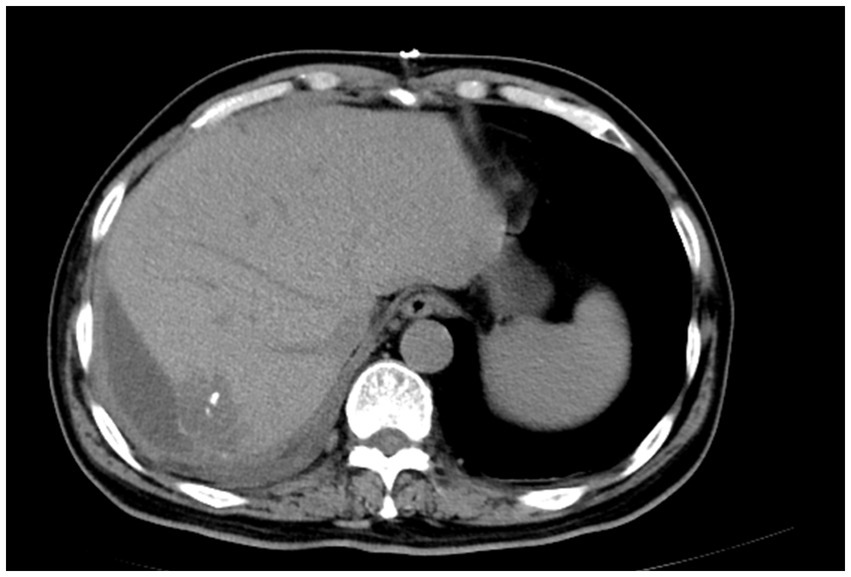

Primary hepatic malignant mesothelioma (PHMM) is an uncommon and aggressive neoplasm with vague clinical and radiological features, posing challenges for preoperative diagnosis. In our case, a lobulated hepatic mass demonstrated a serpiginous peripheral enhancement pattern on contrast-enhanced CT and MRI. This uncommon imaging manifestation has been sporadically documented in previous reports. By consolidating these findings, our report emphasizes serpiginous peripheral enhancement as a potential diagnostic clue for PHMM. Recognition of this pattern may aid earlier detection, improve differential diagnosis, and guide timely surgical decision-making in affected patients.